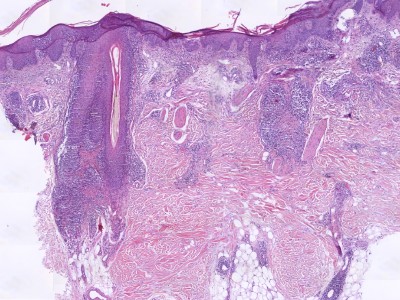

PA:Infiltraat rond de haarfollikels (folliculotropism)

zonder spongiose, met atypische CD4+ T-lymfocyten. Vaak folliculaire mucinosis.

Andere kenmerken kunnen zijn verwijd infundibulum, perivasculaire en periadnexale

dermale infiltraten, Langerhans cellen, eosinofielen en plasmacellen, infiltraten

rond zweetklieren (syringotropisme). Weinig of geen epidermotropism. De lymfocyten

kunnen klein zijn, gemiddeld, of groot blastocytair. Soms CD30+.

![Histologie folliculotrope mycosis fungoides (click on photo to enlarge) [source: Kevin Kwee / Afdeling Pathologie MUMC] Histologie folliculotrope mycosis fungoides](../../../pacoupes/thumbnails/folliculotrope-mycosis-fungoides-1.jpg) |

![Histologie folliculotrope mycosis fungoides (click on photo to enlarge) [source: Kevin Kwee / Afdeling Pathologie MUMC] Histologie folliculotrope mycosis fungoides](../../../pacoupes/thumbnails/folliculotrope-mycosis-fungoides-2.jpg) |

ingescande coupe (zoom) |